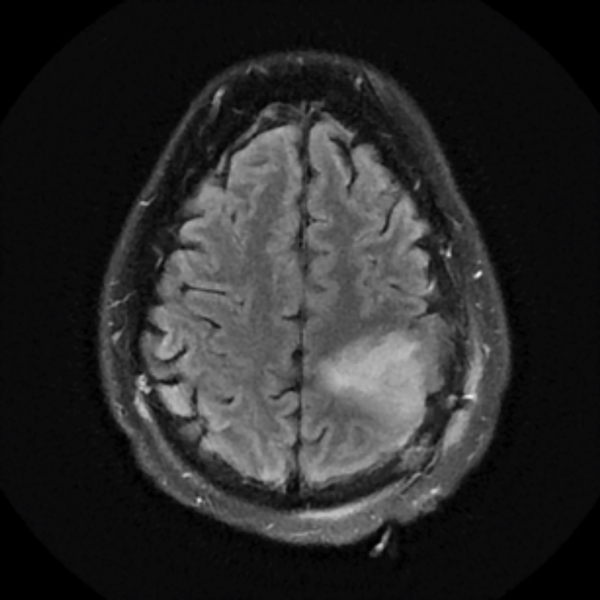

July 2019

A 43-year-old man had symptoms of cognitive impairment and frequent jerking involving his right arm.

A brain MRI showed an increased T2 signal in the left frontoparietal area. His tumor was non-enhancing. He underwent a partial resection of the tumor performed by NSPC neurosurgeon Ramin Rak, M.D., with intraoperative monitoring revealing eloquent motor cortex involvement anteriorly. The pathological diagnosis was WHO grade 2 oligodendroglioma.